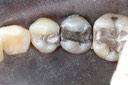

Mark Chun #17 pre-op